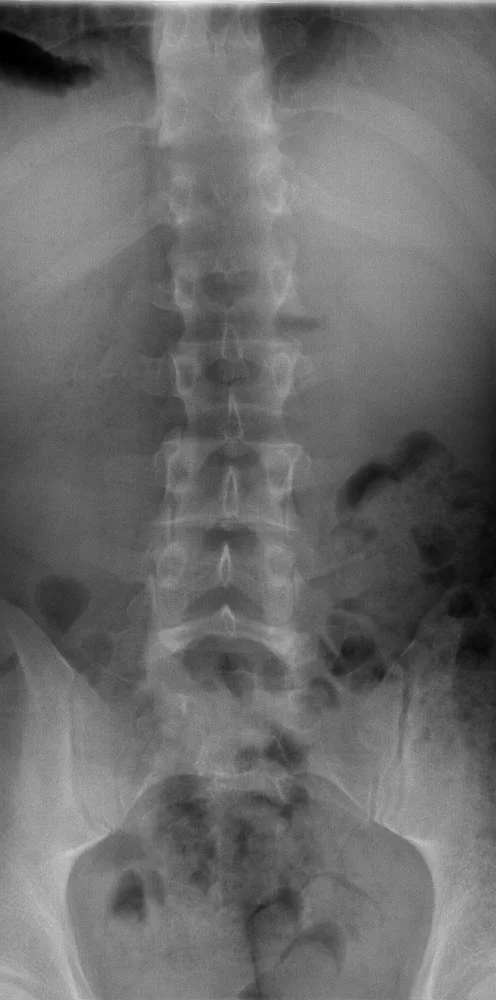

Здравствуйте,с недавних пор появились боли в позвоночном отделе спины,хочу проверить,что не так и залечить проблему. Возможно кто то сможет подсказать где в Харькове это можно сделать или к кому обратиться?

Хочу добавить немного информации,сделал рентген поясничного отдела(прилагается).В заключении написали остеохондроз.